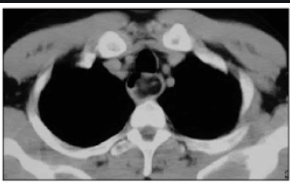

Lipomatose mediastinal

Deposição de gordura no mediastino; causa benigna de alargamento mediastinal.

Mais comum no mediastino superior;

Causa: Uso de corticóide, Sindrome de cushing, obesidade;